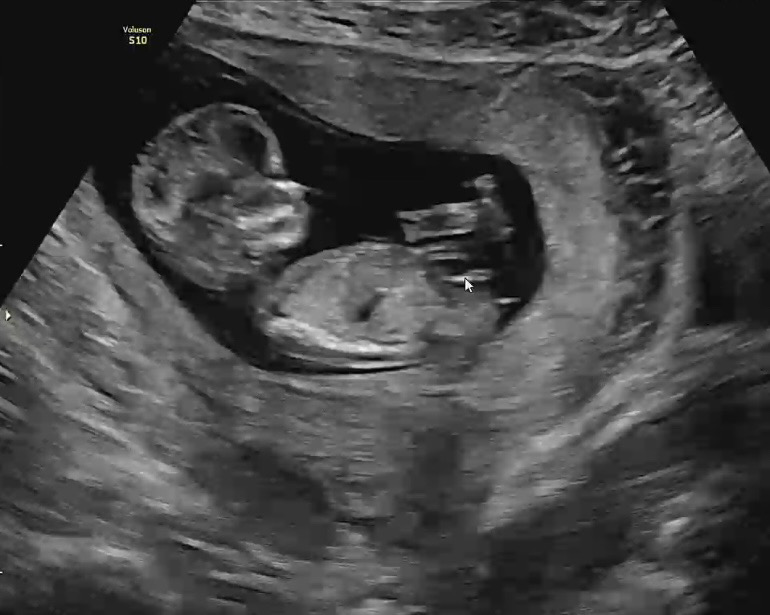

12주2일 각도법 보일까요?!

12주2일 각도법 보일까요?!! 투표해주세요 각도법 고수님들!!